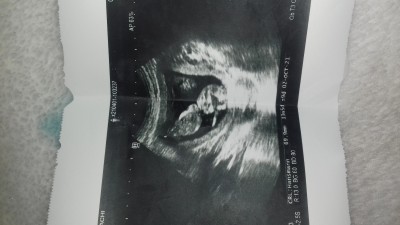

Slm ben 13 hafta üç günlük cinsiyet için gitim ve kıza benziyor dedi ama tm emin değilim yanıltma payı var dedi sence kıza mı erkeğe mi benziyor tahmin edebilirmsniz

Gebelik haftası 17- haftalik